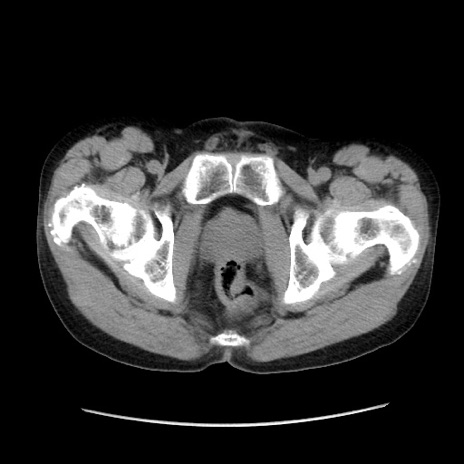

症例37(横断像)

【症例】40歳代 男性

【主訴】腹痛

【現病歴】4時間ほど前に電車に乗車中に臍部上より腹痛出現。徐々に増悪し起立困難となり、救急外来受診。生ものは数日食べていない。今朝お雑煮を食べた。

【身体所見】BT 36.8℃、BP 117/84mmHg、HR 91/min、SpO2 97%、苦悶様、腹部:臍上部広範囲圧痛あり、反跳痛±

【データ】WBC 8100、CRP 0.03